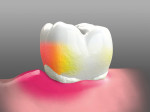

SoproCARE has three unique modes—Daylight, Cario, and Perio (Figure 1 and Figure 2). When used in this order, a predictable clinical protocol is developed that, with proper training, can be implemented by general practitioners and other members of the dental team during the prophylaxis appointment.

The next step is imaging in Cario mode, which uses blue light for visual detection of enamel breakdown and caries. Any carious lesions that were identified in Daylight mode will be readily detectable through the red color in Cario mode (Figure 1).